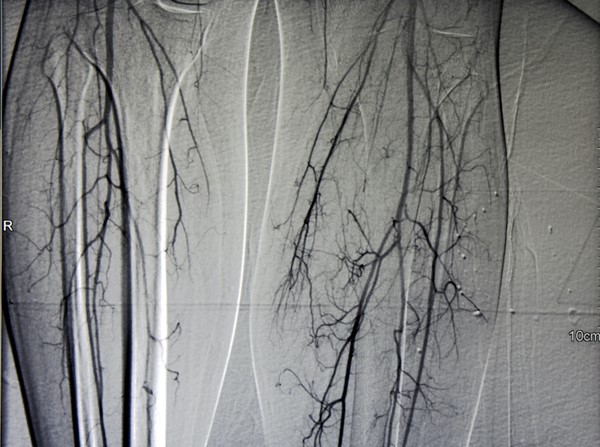

Prior to referring a patient with AU to a vascular specialist, wound clinicians may wish to consider ordering an arterial duplex ultrasound to help expedite decisions about revascularization. Other vascular imaging modalities can be ordered by the vascular specialist, if the patient is identified as a surgical candidate. See Table 4 for a comparison of imaging modalities.

-

2BGuidelines suggest duplex ultrasound imaging (DUS) as the initial arterial imaging modality to determine the presence, extent and severity of arterial disease and to help inform decisions about revascularization (Grade 2B).[5]

- Rationale: DUS provides information on the anatomic location and extent of disease as well as information about flow volume and velocity. DUS imaging is usually the first choice for vascular imaging and in some health care settings may be the only modality available. In some cases however, it may be appropriate to proceed directly to computed tomography angiography (CTA), magnetic resonance angiography (MRA) or catheter digital subtraction angiography (DSA) instead of DUS imaging.

Advantages: although DUS has been shown to be inferior to other imaging techniques such as digital subtraction angiography (DSA), DUS offers many advantages as a first-line imaging modality, including its noninvasive nature, low cost, no iodinated contrast media, no ionizing radiation, and wide availability.[5][86]

Limitations: DUS is time-consuming and highly operator dependent. Furthermore, calcification may result in an incomplete examination. DUS is also poor at estimating collateral blood supply and reserve.[5]

For patients who are candidates for revascularization, additional vascular imaging is indicated. Invasive vascular imaging (e.g. CTA, MRA, catheter angiography), should only be obtained after the decision to intervene has been made. The decision to intervene is based on history and physical examination and on the potential for improvement in quality of life, and not solely on anatomical findings.

2BIn order to guide revascularization planning for patients who are candidates for revascularization, guidelines suggest evaluation with noninvasive vascular imaging studies (i.e. computed tomography angiography, magnetic resonance angiography) before invasive catheter angiography (Grade 2B).[5][87][88]

Rationale: In candidates for revascularization, high quality arterial imaging helps plan and guide the intervention. Choice of imaging modality varies according to the availability of equipment and local expertise, and according to history and physical examination. For patients who are suitable candidates for limb salvage, complete diagnostic angiography that includes the ankle and foot should be performed before revascularization is attempted or denied.[5]